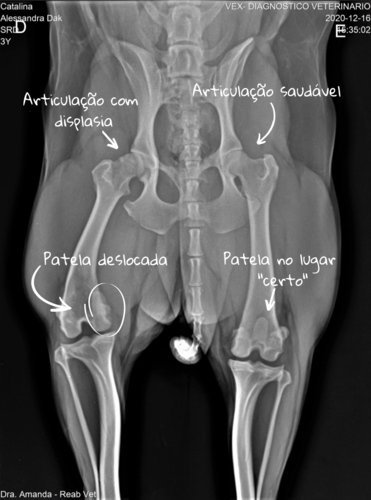

Durante 2020 notei que ela estava andando com dificuldade e sempre meio dolorida e com isso descobrimos que ela tem displasia coxofemoral do lado direito (articulação coxofemoral direita com arrasamento e esclerose acetabular segundo o laudo do raio x) e luxação na patela direita (ou seja, a patela fica se deslocando pra "dentro", o que causa dor e a deixa manca até "voltar" para o lugar.

In 2020, I noticed she was having a hard time walking and kinda sore, took her to the vet and found out that she has hip dysplasia and also a patellar luxation on her right leg. Which makes her limp for a few days until her kneecap gets back in place.